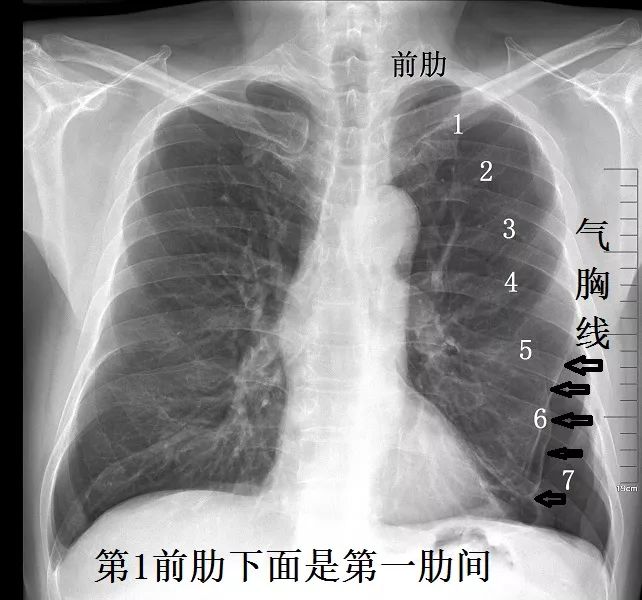

关于流动性差的气胸的X片,先看看慢性不流动气胸,胸片如下:

下面是急性流动性气胸,气往高处走,对比一目了然:

由此可见,对于气胸,CT和X片各有优劣。

顺便说说,胸片诊断气胸,一定要会分辨肺纹理。肺纹理消失的地方,才考虑气胸,不可看见肩胛线就误以为是气胸。